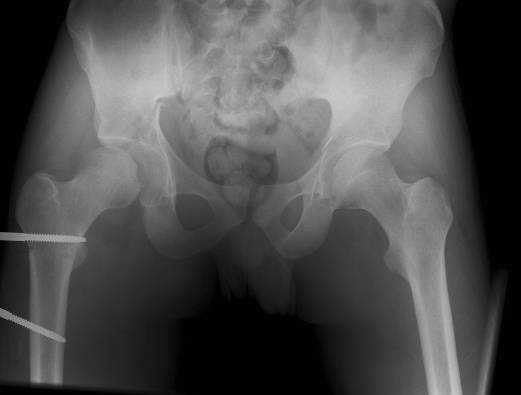

The details of the fracture are not so clear from the images sent...would you be able to send along an AP and Judet images as well as some additional axial images above and below the joint?

I’m not so sure that your patient has a Tr+PW pattern based on the images sent...maybe the fracture’s exact name won’t matter in the long run, but it’d be great to see enough images to make an accurate comment.

Without complete CT images and/or oblique radiographs, it's difficult to answer your question definitively, but it appears that there may not be a posterior wall fracture that requires a posterior approach. A successful reduction through an ilio-inguinal approach will have a faster recovery, and not risk SGN injury or heterotopic ossification.

Here are some more axial images. What is your opinion as for the timing of the operative treatment?